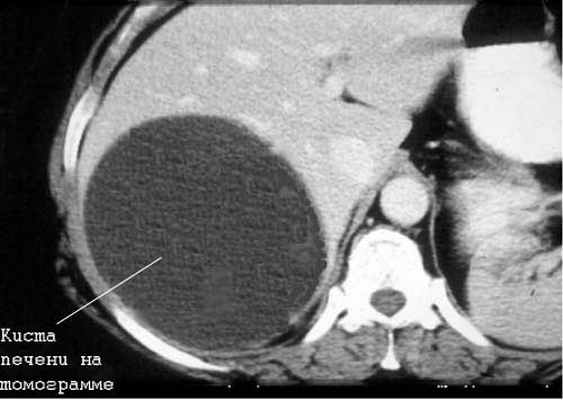

Киста печени

Чаще встречаются непаразитарные кисты. Учитывается возможность поликистозной болезни, а также солитарных и множественных истинных и ложных кист печени.

Большинство кист небольшие (диаметром 1-5 см), чаще встречаются у женщин. Значительная часть их имеет бессимптомное течение. У ряда больных отмечаются боли в правом подреберье, у одних — постоянные, у других — периодические. Существенную помощь оказывает использование УЗИ и КТ (или ЯМР), обладающие высокой разрешающей способностью. Необходимо учитывать возможность поликистоза печени.

Дифференциальная диагностика простых кист проводится также с паразитарными кистами печени (эхинококкоз). В пользу последних говорят положительные реакции с эхинококковым антигеном и Кацони, а также обнаружение в зоне опухолевидного образования обызвествлений, хотя и гемангиомы изредка могут обызвествляться.

Часть непарзитарных кист печени также подлежит оперативному лечению в связи с реальной возможностью их разрыва, инфицирования и кровоизлияния в просвет кисты. Кроме того, быстро растущие крупные кисты приводят к нарушению функций печени вследствие атрофии и замещения печеночной паренхимы кистозным образованием. Среди операций наиболее часто используют резекцию печени, перицистэктомию и вылущивание кисты.

В последние годы широкое распространение получили транспариетальные пункции кист под контролем УЗИ или КТ. После аспирации содержимого в просвет кисты вводят 96*раствор этилового спирта для склерозирования внутренней оболочки кисты. Эта операция эффектина приразмере кисты до 5 см. Если нет эффекта от данных способов лечения или киста имеет больший размер, показана операция — лапароскопическое иссечение участка кисты с последующей деэпителизацией внутренней оболочки кисты аргонусиленной плазмой или расфокусированным лучом лазера. Аналогичная тактика используется и при поликистозе печени. При осложненном поликистозе печени (нагноение, кровотечение, озлокачествление, сдавление крупными кистами желчных путей, воротной или полой вены) показано оперативное лечение. Обычно выполняют фенестрацию (вскрытие выступающих над поверхностью печени кист) с последующей деэпителизацией внутренней оболочки кисты.